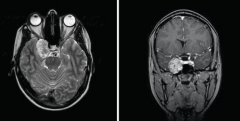

脑膜瘤急性复发性出血危及生命

原发性脑瘤患者自发性颅内出血的发生率在文献中从1.4%到10.0%不...